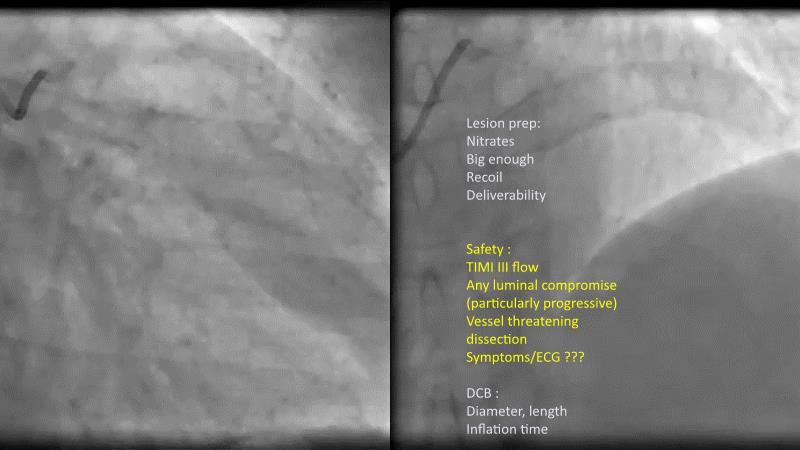

DES and DCB, can these two technologies be complementary for the treatment of the same patient? What are the advantages and how to proceed? You will know everything by watching this presentation based on concrete cases.